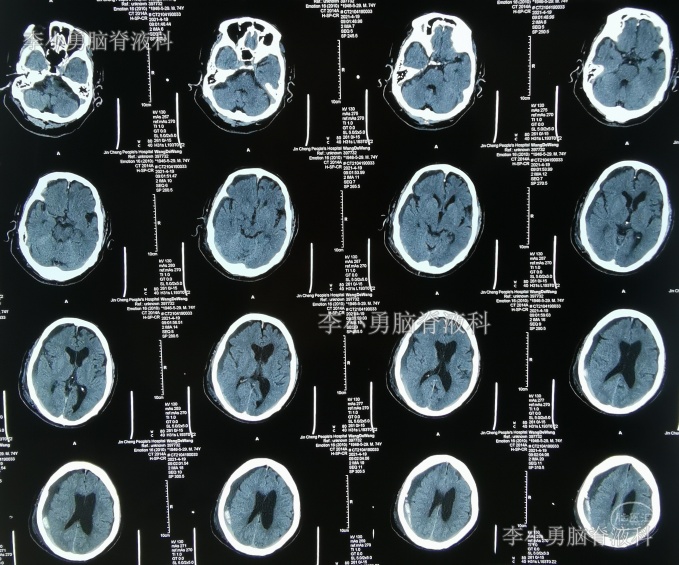

拔除引流管后8天时间内,间断有右侧额颞部站立时疼痛,分别于2021年4月24日和2021年4月27日,查头部CT示硬膜下血肿增多(图-7、图-8),平卧位继续观察。

图-7:2021年4月24日头部CT

图-8:2021年4月27日头部CT

因站立时头痛,该院医生建议再次做引流术。

2021年4月30日(腰大池腹腔分流术后33天,即拔除硬膜下血肿引流管11天),因坐立时仍头痛,转至第5家山西省另一所省级三甲医院,查头部CT(图-9)后建议继续平卧位。

图-9:2021年4月30日头部CT